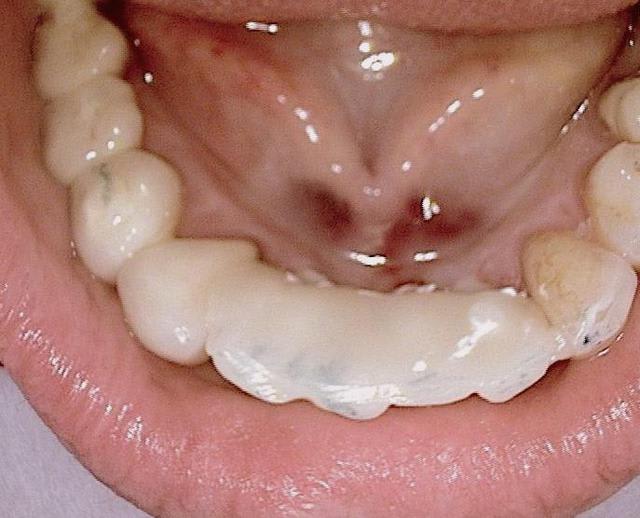

ton commentaire m a fait remarqué que je n´ ai pas mis la photo de la prothèse du cas! merci ! :-)

ci dessous

cordialement

Folie1 ofu0m9 - Eugenol

Folie2 z7edyr - Eugenol

Folie3 aeqhya - Eugenol

Folie4 q9egfx - Eugenol

Folie5 icxmia - Eugenol